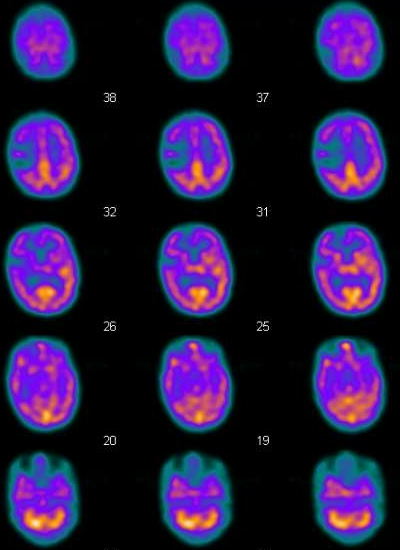

這是個歷史事件,當時的情況是,有個病人要來做Brain的perfusion,他顱內的血管有阻塞,因此可預期的在注射完ECD之後,應該可以看到腦部影像的缺損,不過如果事情都能夠發展的這麼順利,那麼科學就不會有進步了。事發的經過是這樣的,原本要注射的藥劑是Tc-99m ECD,可是不小心拿到旁邊的Tc-99m MDP,10:30注射的,接下來原本要做bone scan要打針時,就找不到Tc-99m MDP來注射,此時才發現打錯病人了,這時只好讓bone scan的病人回病房等,先緊急補叫一支MDP讓他用,接下來就必須面對這個打錯藥的病人了,我們的選擇有幾個,第一是跟病人坦承打錯藥了,請病人下次再來,同時詢問病人是否要做一次bone scan看看身體骨頭的狀況,不過坦白講,我們不喜歡這個選項,因為很有可能會讓事情發展到失控的狀況,因此我們採取了另一種方式來處理,就是請原本在外面等的病人進來,跟他說剛打針的劑量有點不夠,因此要再幫他加一點藥,坦白講這步驟還挺有風險的,於是我們替病人注射了ECD(11:00),當時我們的想法是,因為兩個藥物的分布區域並不相同,Tc-99m MDP沒有辦法穿透BBB,因此並不會干擾到腦部的影像,所以我們在刻意稍等了一下,在12:30開始做Brain的掃描,那時Tc-99m MDP在軟組織的清除也應該差不多了,照相的時候,在使用high resolusion collimator的情況下,每個頭的count數約在4~4.5 k counts,和平常相比並沒有明顯高出多少,因此理論上影響應該不會太大,從原始影像來看,就有點醜了,是一種骷顱頭加腦袋的影像合體,其實這時候就有點擔心,但是也只能硬著頭皮把影像照完,才能做下一步的決定。

結果揭曉,我放上當天與正常影像的比較圖。

| 整體count為77~82,MDP的確增加了很多count數,此外brain的影像加上了骨頭的影像,看起來就怪怪的 | 整體count為33~35,所看到的就是完全腦部的影像,左右的位置都相同,但是我忘記把影像調成一樣大了 |

| 在腦部外,可以看到略略的頭骨影像 | 正常的腦部影像 |

最後報告的影像,我們用mask盡量去除了外圍的頭骨,所以影像上看起來還可以交代得過去,但是這樣的錯誤,還是要非常小心,別再犯了。 |

正常的影像 |